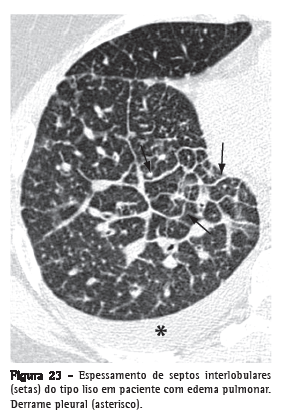

Espessamento de septos interlobulares

Espessamento dos septos de tecido conjuntivo que separam os lóbulos pulmonares secundários. Caracterizado na radiografia por finas opacidades lineares, também denominadas de linhas B de Kerley.

Usualmente encontra-se em íntimo contato com a superfície pleural lateral, junto aos seios costofrênicos, apresentando um ângulo reto em relação à parede. Atualmente os termos "linhas septais" ou "espessamento septal" têm sido preferidos ao invés de linhas de Kerley. Na TCAR (Figura 23), o espessamento dos septos interlobulares é caracterizado pela presença de opacidades lineares que delimitam os lóbulos pulmonares secundários, mais facilmente caracterizável na região subpleural, onde tem aspecto de linhas perpendiculares à superfície pleural.(3,44) Nas regiões centrais dos pulmões, o espessamento dos septos de lóbulos adjacentes resulta no aspecto de arcadas poligonais. O espessamento septal pode ser secundário à alteração de qualquer um de seus componentes (veias, vasos linfáticos ou tecido conectivo) e é um achado comum a várias alterações pulmonares, embora sua presença seja particularmente destacada nos casos de edema pulmonar e de linfangite carcinomatosa. O espessamento septal pode ser do tipo liso (Figura 23), nodular (Figura 24) ou irregular. Essa diferenciação pode ajudar no diagnóstico diferencial das diversas etiologias.